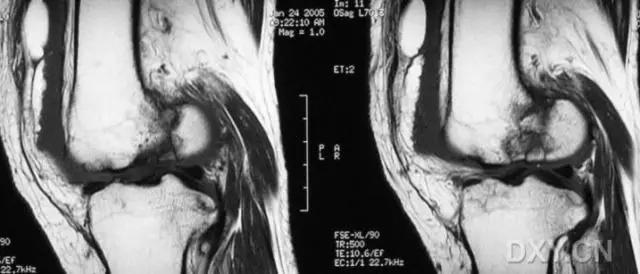

5. Hoffa 骨折

指股骨远端冠状面的骨折。

病例 1:一般股骨髁间、髁上粉碎骨折中含 Hoffa 骨折的不少见,但单纯后髁骨折则很少见。

正位片

侧位片

水平位 CT

第 2 例

第 3 例